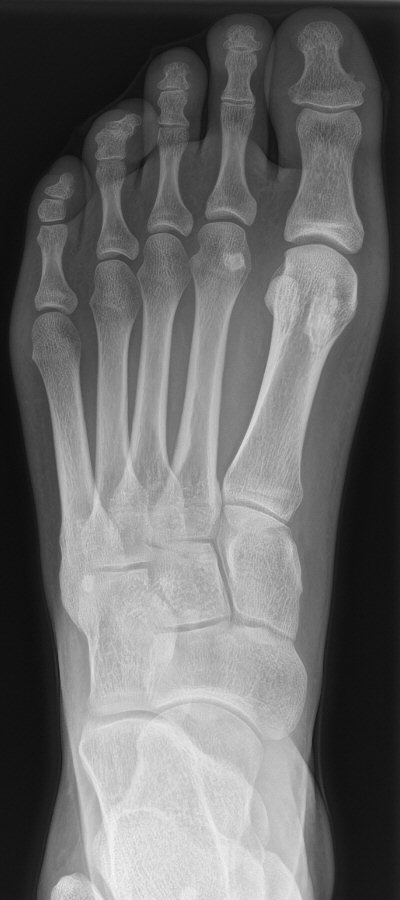

Fraktur på mediala sesambenet, första två bilderna efter en månad, tredje bilden efter 5 månader